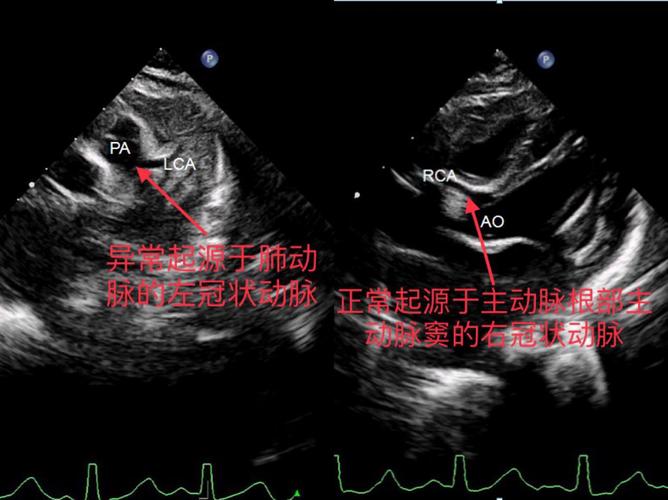

图1 术前心脏彩超明确诊断患儿左冠状动脉起源异常